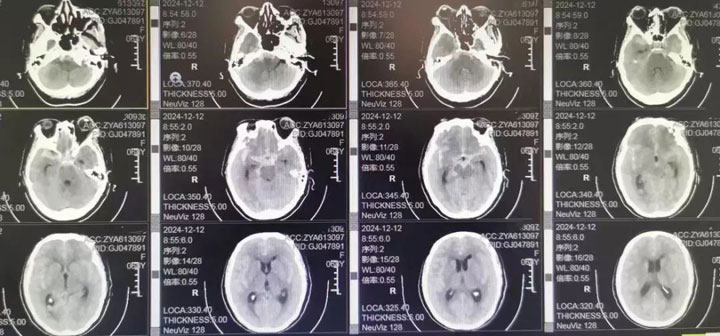

3个月前,患者因突发剧烈头痛被紧急送往东方总院,入院时意识模糊不清,烦躁不安,行头颅CT检查提示蛛网膜下腔大量出血,按照Hunt-Hess分级为3级,生命垂危。

入院后吴全主任立即安排科室医生陪同患者紧急行头颅CTA检查提示双侧后交通动脉瘤破裂出血,结合头颅CT,考虑右侧后交通动脉瘤为责任动脉瘤。患者为镜像动脉瘤,很少见,一侧动脉瘤破裂出血,另一侧也有破裂出血的风险。